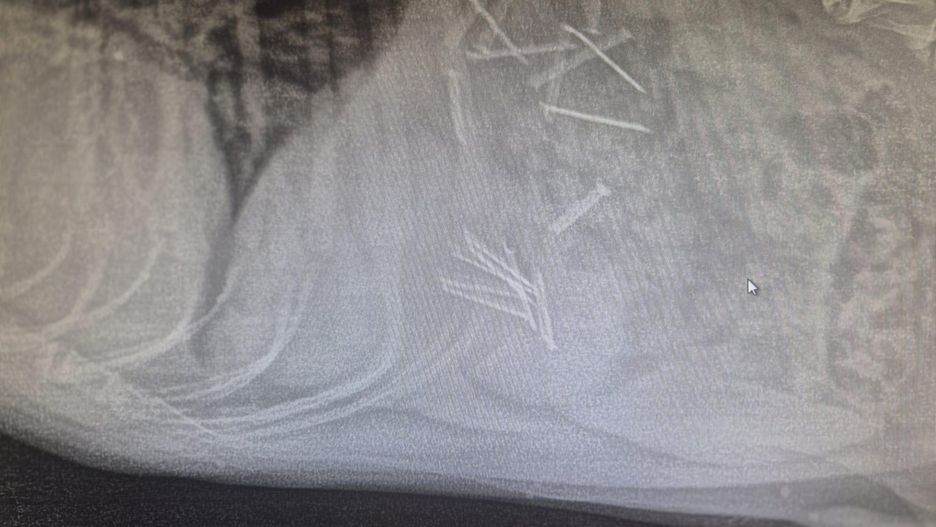

Weterynarze z gabinetu w Wadągu pilnie zajęli się psem. Z jego żołądka usunięto aż osiemnaście gwoździ oraz fragmenty mięsa. Jak podkreślają lekarze, ten incydent jest przykładem skrajnego okrucieństwa wobec zwierząt.

Na szczęście szybka reakcja opiekunki psa pozwoliła uratować jego życie. Klinika opublikowała zdjęcia rentgenowskie oraz materiały wyjęte z przewodu pokarmowego zwierzęcia, co stało się mocnym dowodem na niebezpieczeństwa czyhające na mieszkańców i ich czworonogi.